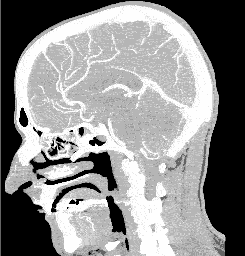

This very expensive scan was required just to get pain killers. The pain was very severe. I tried some aspirin, etc to no avail. After 4 days at home with pain increasing daily, i was persuaded to ride into a local hospital and i hoped to try a little hospital pain killer relief. To my disappointment pain killers were promised only after the X-ray scans (CT angiography). This took many hours to wade through with many useless delays. After finally obtaining a bit of pain killer i decided hospitals and medical protocol were clearly wrong for me. Yet thinking did improve with less pain. I wanted to escape from the gloomy, institutional mind set. Only drugs were offered if one could pay the multiple protocol costs. If one could pay for a bed priced higher than luxury hotels. Sure, charge anything to my name, very funny. Hide the price tags. Little hospital signs encouraged comers like me not to worry about payment!!! Ha, they would have crippled my life, had i depended on them. So, with gradual cognition i increasingly wanted to go home . I had come only in hopes of acquiring a little prescription pain killer, perhaps like a dental situation. The severe head ache had heavily burdened rationality. One pays royally for this or luckily discovers better alternatives. I did find a far superior pain remedy which costs nothing at all. It is a totally-cost-free-remedy and some traditions prescribe it.

To summarize quickly, my CT Angio scan results revealed a skull fracture, blood on the brain but fortunately no aneurysms. It seems logical that "blood on the brain" would cause severe head-ache pain, due to normal blood pressure. (When the head is gravitationally level with the heart, that is. Sitting up reduces the blood pressure on the all-important blood brain barrier.) However, it is illogical that a modern science would hide the most appropriate remedy from head-trauma victims, (in favor of monopolistic remedies-- Masking the pain instead of relieving the high pressure on the blood-brain-barrier). I largely attribute my healing to intensive nutrition along with self styled mental and spiritual discipline. I have always respected high-quality dietary protocols and "dietary supplements". Especially when i don't have time to shop around for better ranking food, nor time for proper preparation. I generally admit that food preparation should be prioritized. I was especiallyappreciative to find specific diet and supplement protocols put together by garynull.com.